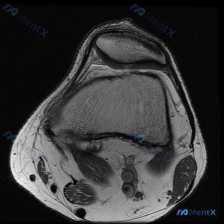

踝关节MRI显示软骨异常,这个位置的病变你能一眼抓对病因吗?

影像为踝关节冠状位T2加权单帧图像,清晰度可,主要发现如下:

- 核心异常:距骨穹顶内侧可见局灶性不均匀T2高信号,边界相对清晰,提示该区域骨髓水肿;距骨穹顶关节面不连续,软骨下骨质轮廓稍不平整,信号增高

- 其余骨骼骨髓信号未见明显异常

- 胫距关节间隙可见局限性T2高信号,提示少量关节积液

- 单帧图像无法完整评估韧带,可见的内侧三角韧带无明确连续性中断

- 关节周围软组织无广泛水肿或占位